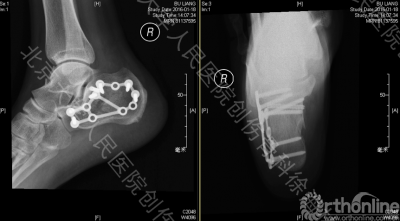

术后CT和X片